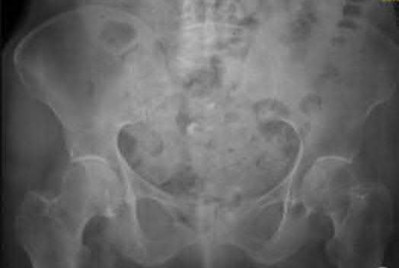

A 35-year-old male sustains an anteroposterior compression (APC) type II pelvic ring injury.

During anterior ring fixation via an ilioinguinal approach, massive hemorrhage is encountered posterior to the superior pubic ramus. Which anomalous anatomical connection represents the classic 'corona mortis'?

Explanation

The 'corona mortis' (crown of death) refers to a vascular anastomosis between the obturator and external iliac (or inferior epigastric) vascular systems. It is located posterior to the superior pubic ramus at a variable distance (average 5-6 cm) from the symphysis pubis and can cause life-threatening hemorrhage if inadvertently disrupted during anterior pelvic ring surgery (ilioinguinal or Stoppa approaches).